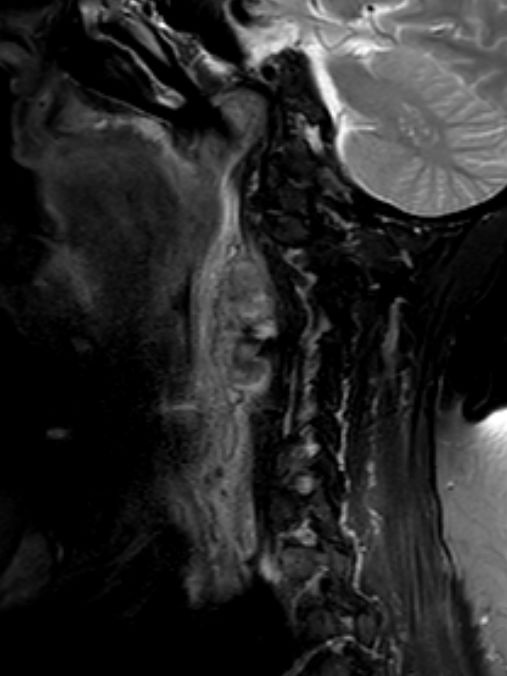

| Diagnostik | 88-jährige Frau mit einer progredientes

Dysphagie. Es besteht eine Raumforderung rechts retropharyngeal. Mukosa intakt.![]()  |